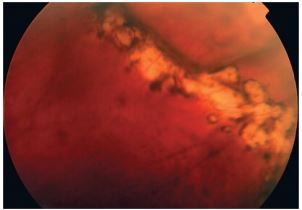

Q

what is this?

A

Lattice degeneration

- increase the risk of RD

- high prevalence of 30% in high myopes

- does not affect vision